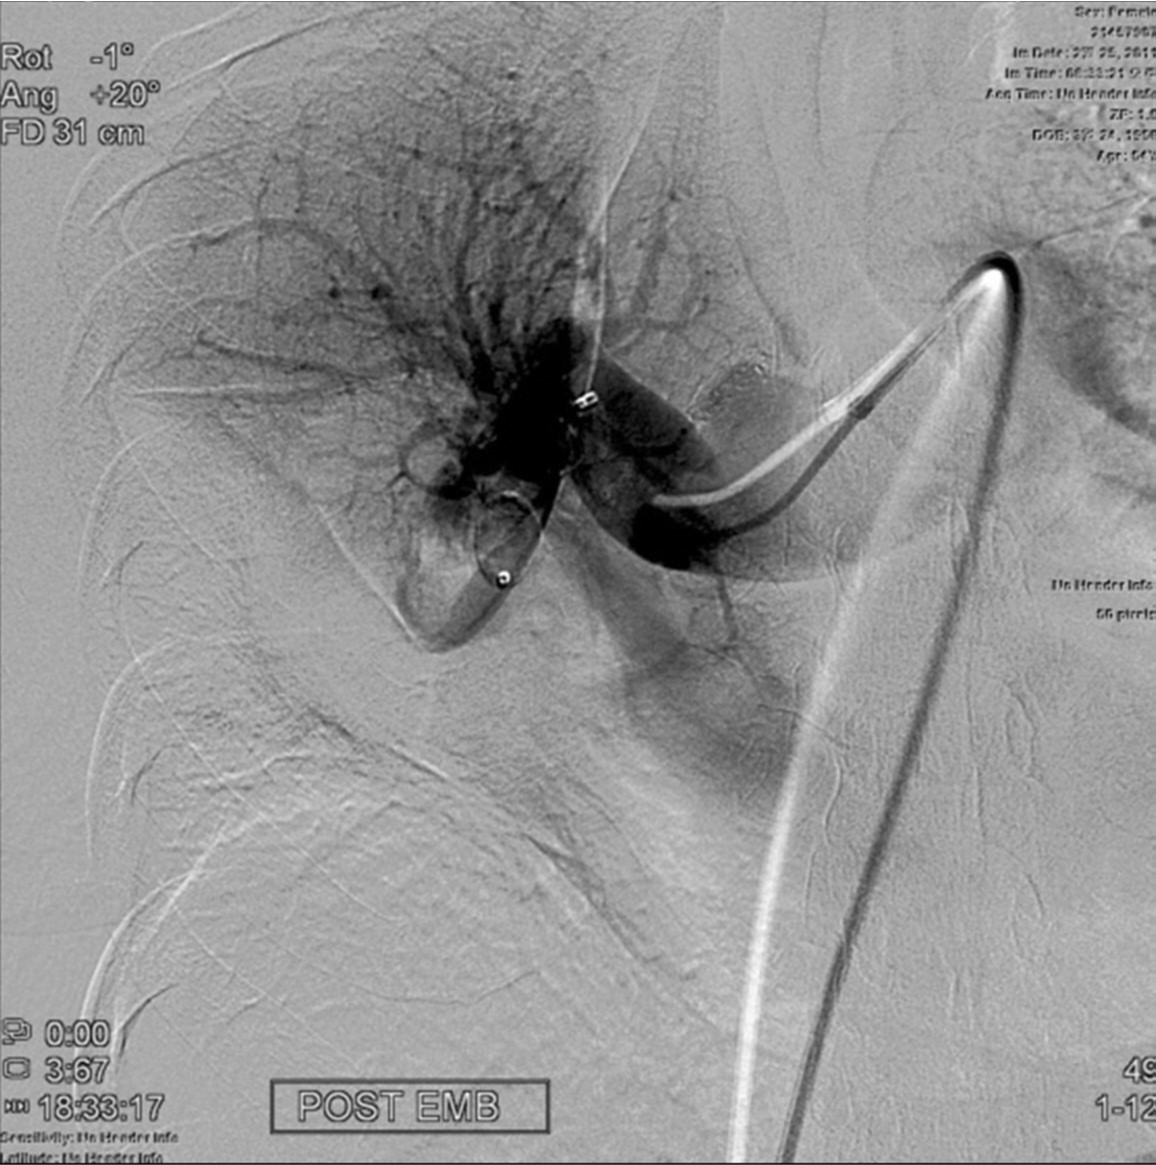

Fig. 4.

Fig. 4. Right pulmonary angiogram obtained 60 minutes after implanting an Amplatzer vascular plug at the right lower pulmonary artery shows complete exclusion of flow to the pseudoaneurysm.